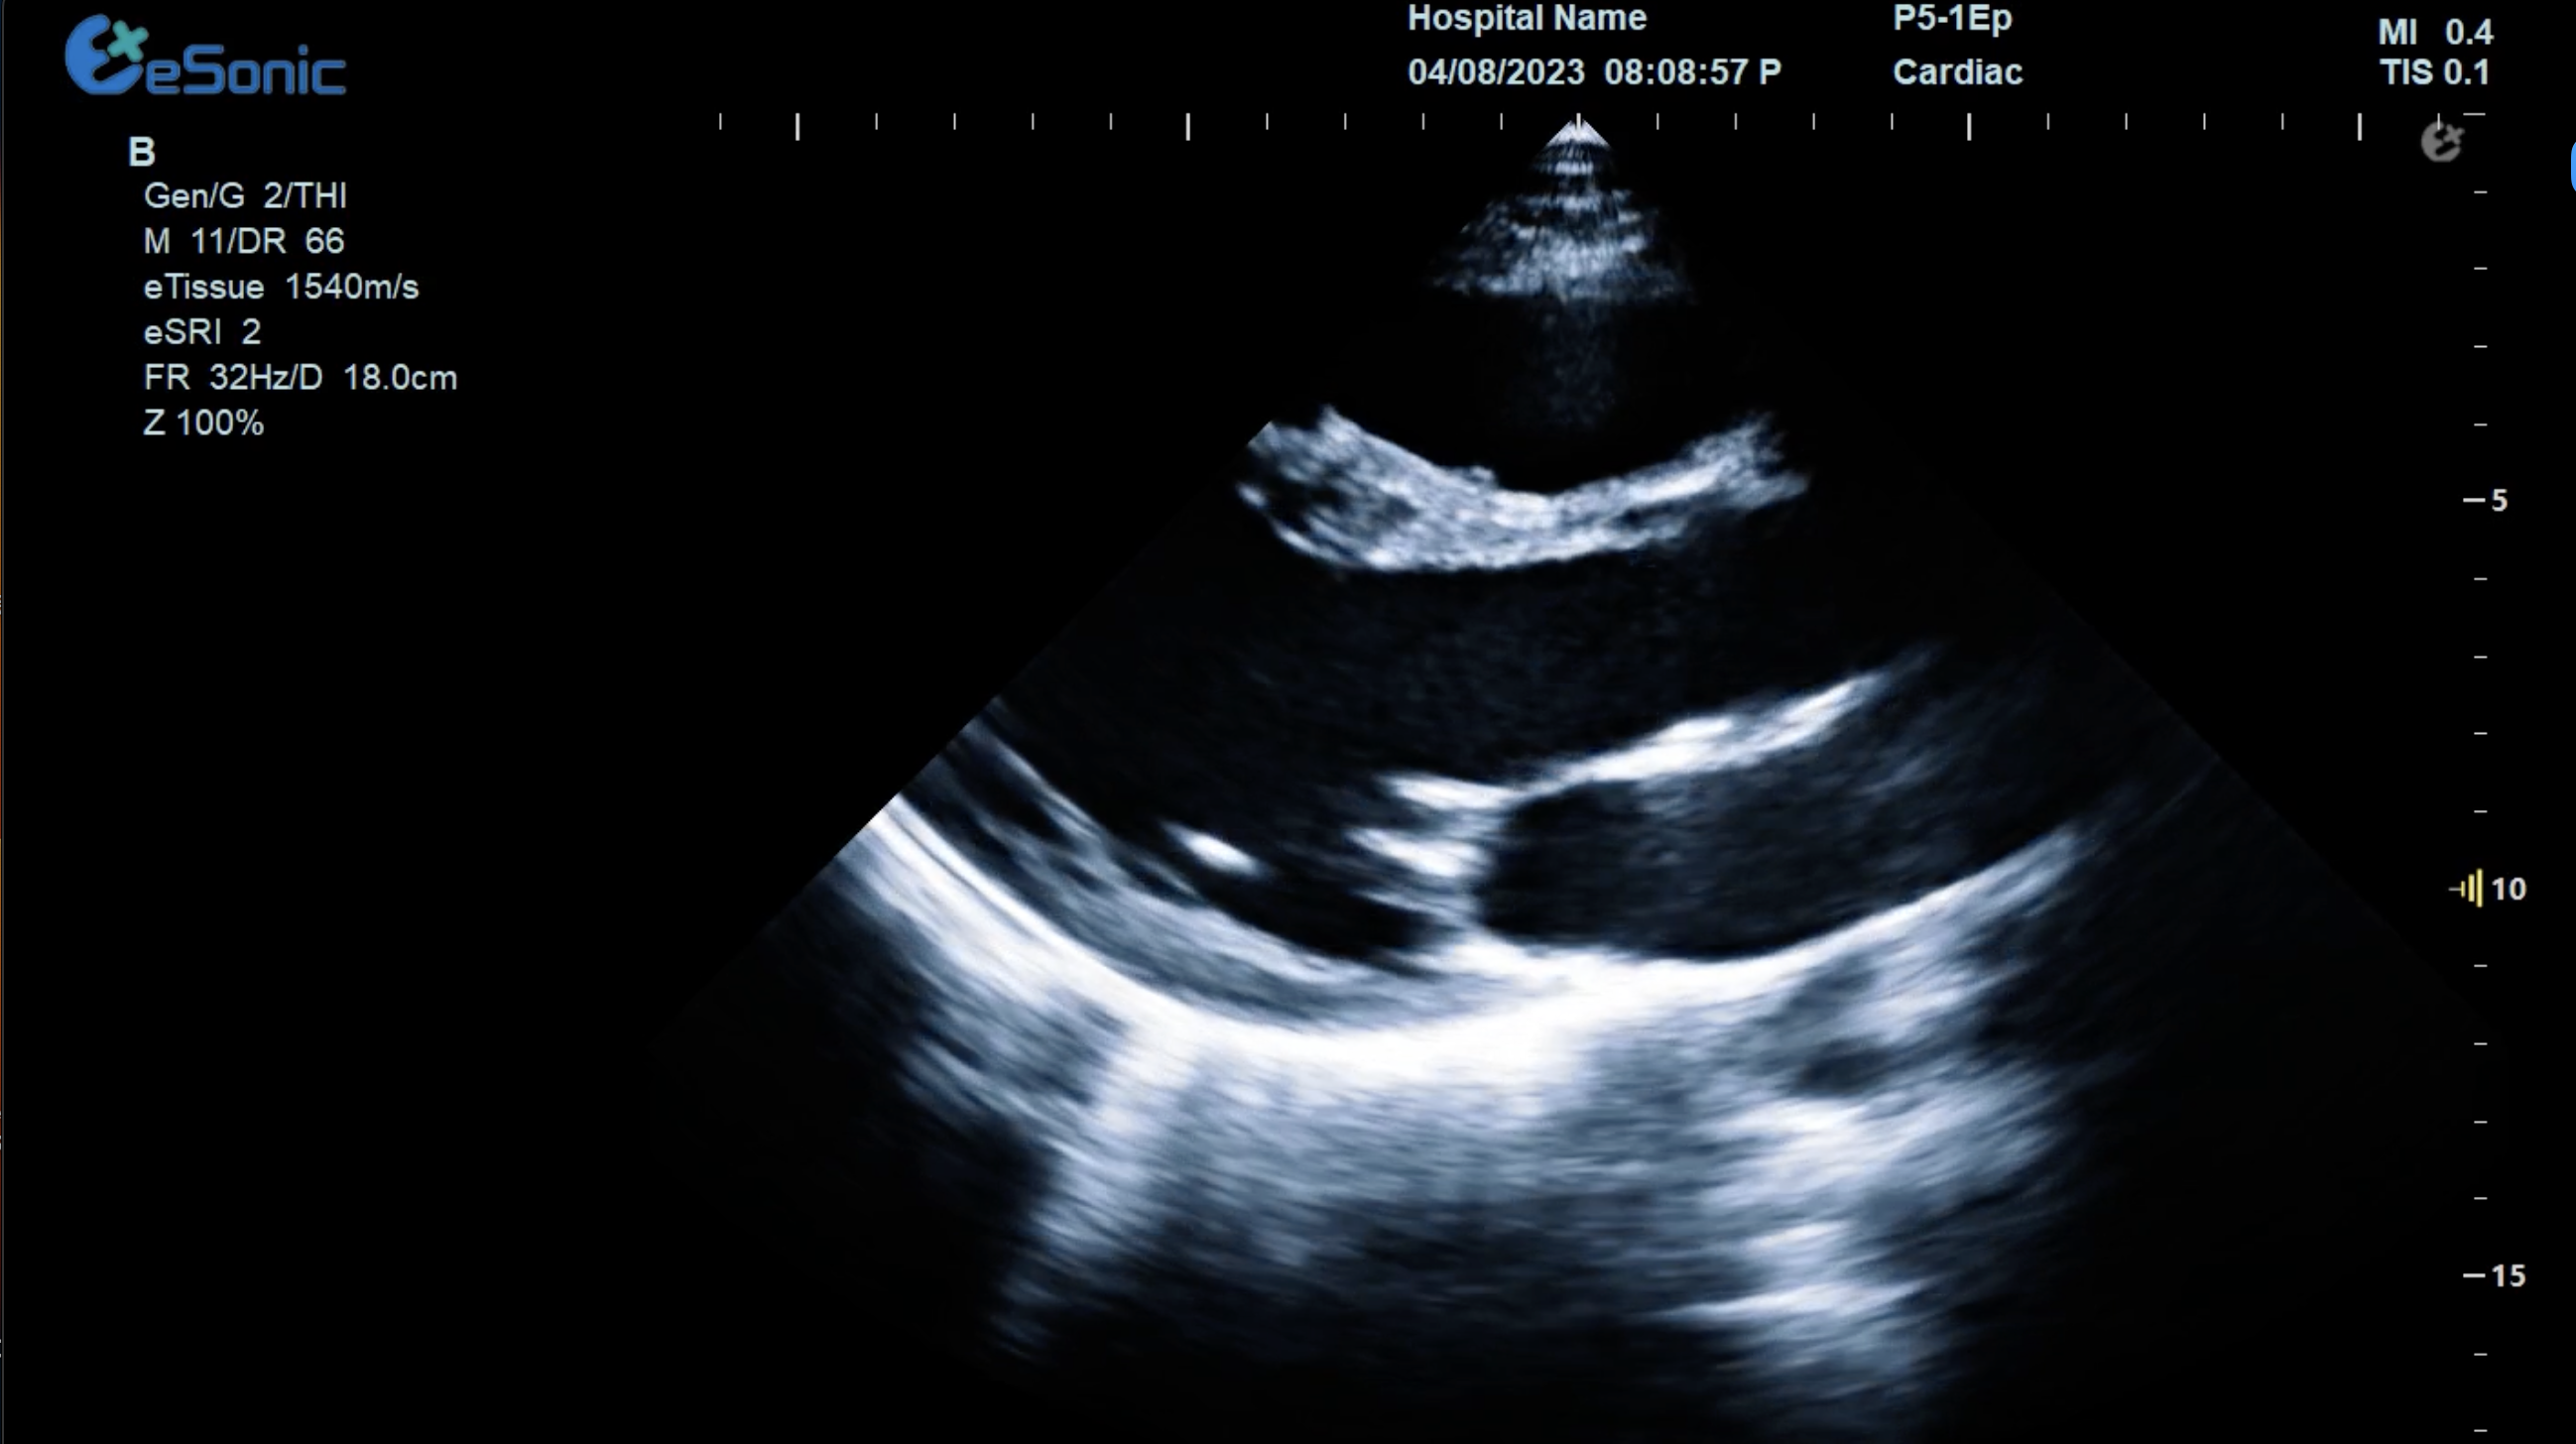

临床病例(一)

女性,68岁,临床诊断:冠心病

超声表现:左房大,左室壁运动幅度明显减低,以室间隔较明显;心包腔内见无回声区,右室前壁8mm,左室侧壁10mm。

冠心病、心包积液